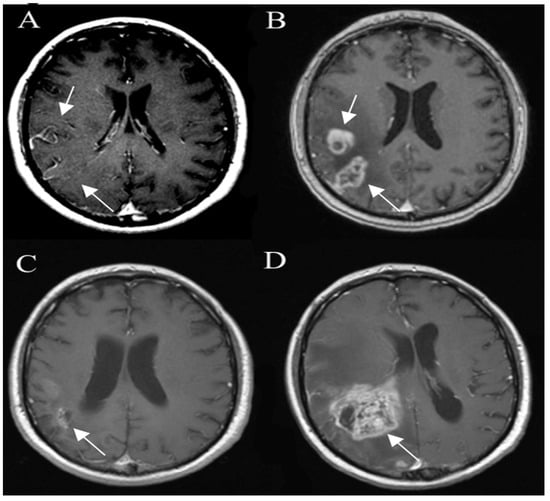

3.6. Posttreatment Imaging

3.6.1. True Progression

3.6.2. Pseudoprogression

3.6.4. Radiation Necrosis